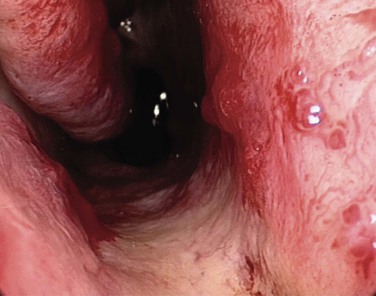

Most anterior epistaxis can be controlled with identification of the bleeding point using a headlamp and cautery. The vast majority of posterior bleeding sites can be identified by endoscopy without general anesthesia.44 The majority of posterior idiopathic bleeds are from the septum, usually from the septal branch of the sphenopalatine artery as it runs submucosally (Fig. 42-14), although some report bleeding from the lateral aspect of the middle or inferior meatus or from the posterior end of the turbinates (Fig 42-15).45 When the site of bleeding cannot clearly be identified with a headlamp, the use of a rigid nasal endoscope by an experienced endoscopist is best. The key is to identify the site of the bleeding and gain control using silver nitrate cautery or bipolar suction diathermy. Recent studies have shown that the use of endoscopic bipolar diathermy treats most epistaxis.46,47 Preparing the nose with phenylephrine or cocaine for its decongestant and anesthetic effects often helps. It is worth noting that phenylephrine has a significant decongestant effect at 6 minutes and maximum anesthetic effect after 9 minutes,48 and time must be allowed for it to take effect. An injection of local anesthetic and epinephrine gives better analgesia, if there is a sizable vessel that needs bipolar diathermy; otherwise, the patient may feel a smarting sensation.

The majority of posterior idiopathic bleeds are from the septum, usually from the septal branch of the sphenopalatine artery as it runs submucosally. The key is to identify the site of the bleeding and to gain control using bipolar suction diathermy. A severe septal deviation can make it difficult to define the bleeding point.49 Control of the bleeding avoids the discomfort associated with nasal packing and avoids admission.50 A cost-benefit analysis of 38 adult patients with epistaxis concluded that £6804 (about $10,260 U.S. dollars) could be saved by avoiding admission in 28 patients.46 Endoscopic cauterization achieves hemostasis in over 80% of patients with posterior epistaxis at the first attempt and over 90% after a second attempt.38 The bleeding point can be cauterized with the help of a nasal endoscope, which has a reported failure rate of 17% to 33%.51,52 Complications associated with this procedure are uncommon, but isolated reports describe palatal numbness from thermal damage to the greater palatine nerve, damage to the lacrimal duct, and possible damage to the optic nerve when cautery is used in a patient who has already had an ethmoidectomy.53 If by some misfortune bleeding is torrential because of trauma to the internal carotid artery in the sphenoid, prompt packing of the sphenoid sinus is required with a firm gauze pack.54 The patient is then resuscitated, and the help of an interventional radiologist is sought.